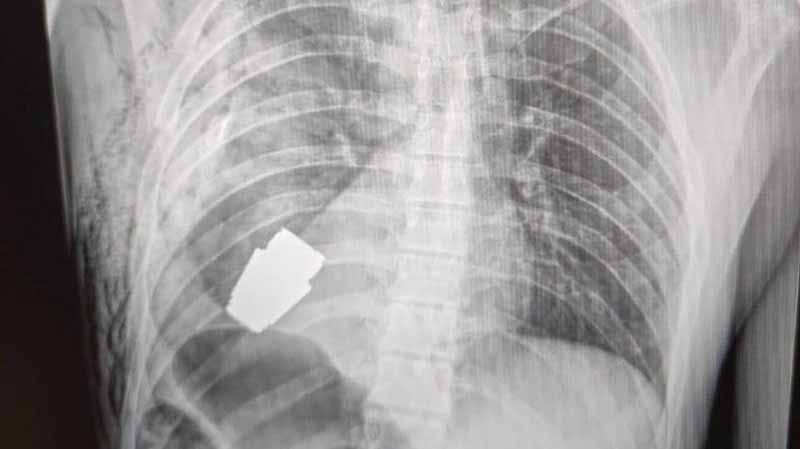

Ουκρανία: Χειροβομβίδα που δεν είχε εκραγεί αφαιρέθηκε από το στήθος στρατιώτη

Χειροβομβίδα που δεν είχε εκραγεί, αφαιρέθηκε επιτυχώς από το στήθος Ουκρανού στρατιώτη σύμφωνα με τους στρατιωτικούς γιατρούς της χώρας.

Οι φωτογραφίες που κοινοποιήθηκαν στη σελίδα του Ουκρανικού Στρατιωτικού Ιατρού στο Facebook τη Δευτέρα δείχνουν με την βοήθεια ακτίνων Χ τη χειροβομβίδα στο στήθος του στρατιώτη.